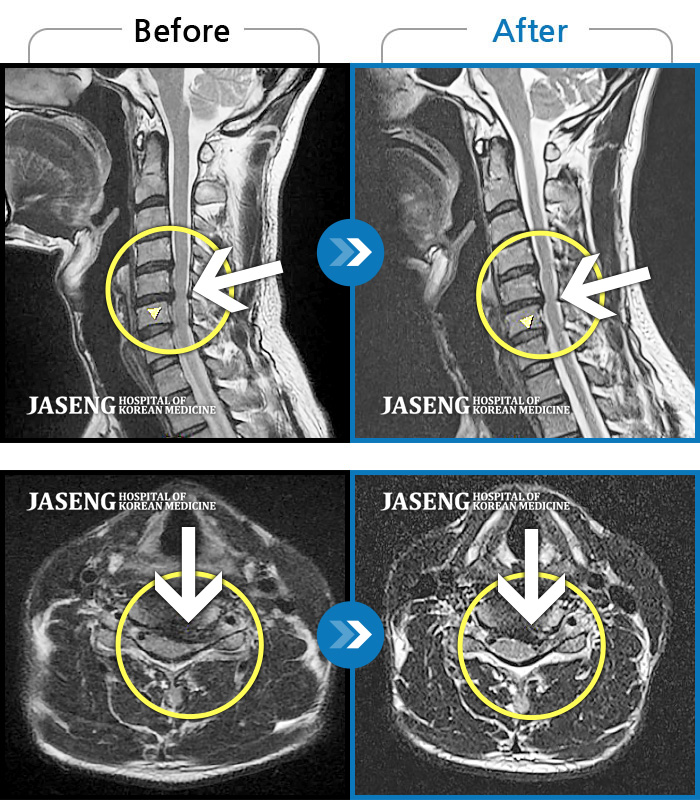

목디스크

광주 · 장영우 원장

후경부 양측부터 승모근까지 묵직한 통증, 좌측 상지 수지까지 이어지는 저린감

촬영시기

2121.04.27 ~ 2121.12.11

2021.12.17

조회수 73